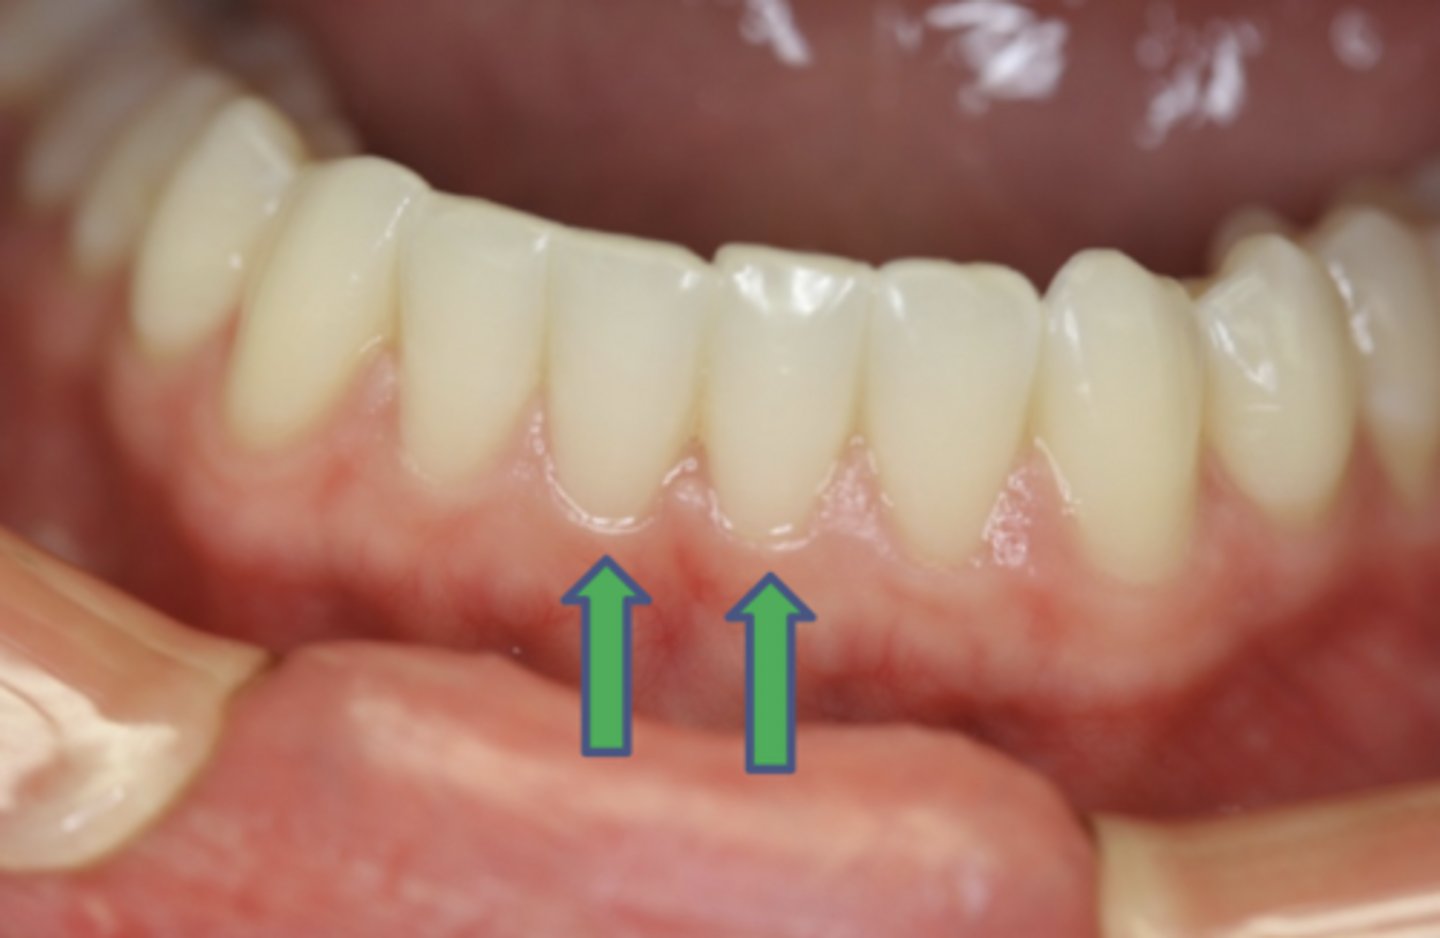

- Root surface is broad and flat with longitudinal depression (calc. collects here)

- Root depression slightly deeper than mesial